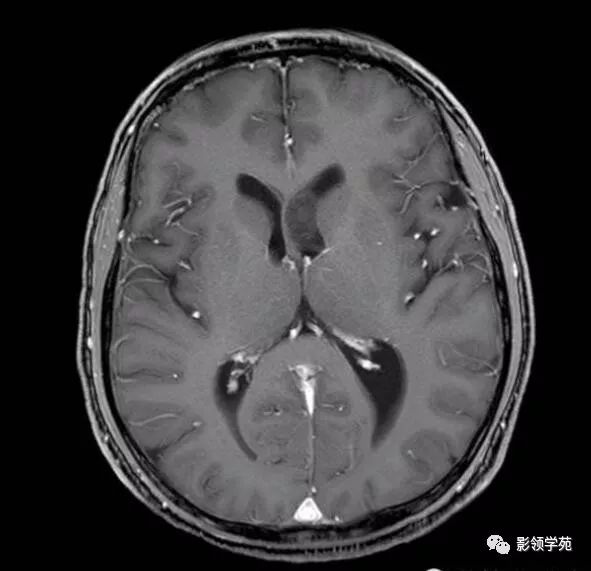

【影像讨论】侧脑室三角区肿瘤,请定性!

图片尺寸800x600